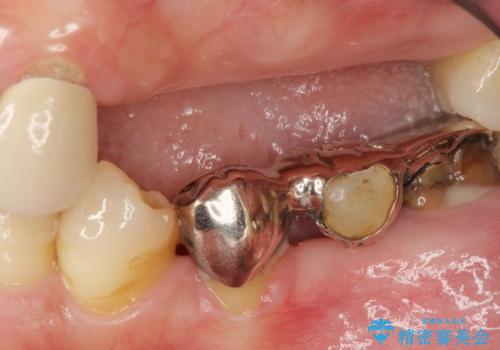

歯周病 全顎治療

- 前歯の見た目、入れ歯による噛めないことの改善を求めて来院されました。

検査により全顎的な歯周病治療、欠損のインプラント補綴、根管治療が必要な状態であることをお伝えし、治療を計画します。